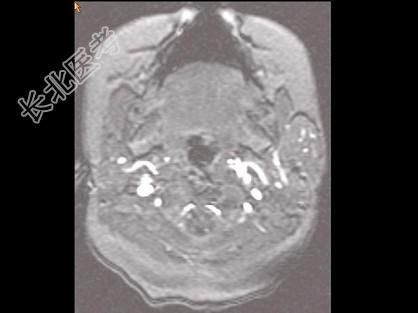

- 单项选择题男,40岁, 左面部渐进性增大的包块,MRI检查如图所示, 最可能的诊断是 ( )

A、左面部毛细血管瘤

B、左面部囊肿

C、左面部脓肿

D、左面部脂肪瘤

E、左面部神经纤维瘤